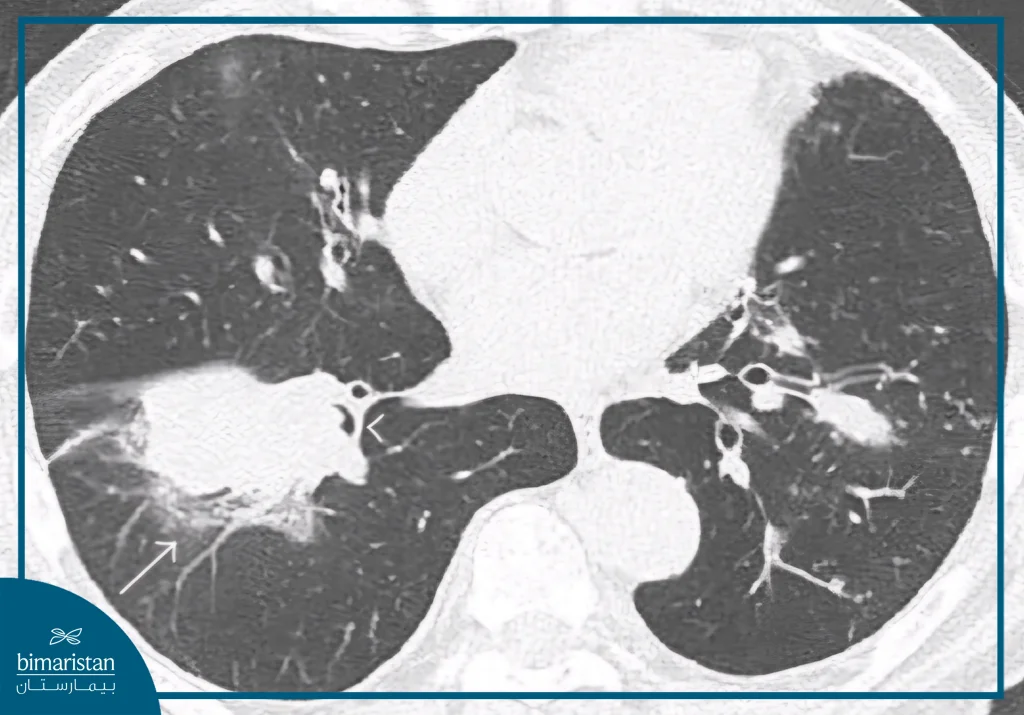

يُشخّص سرطان الرئة الحرشفي عادةً بعد الاشتباه بوجود كتلة في الرئة نتيجة ظهور أعراض تنفسية مستمرة أو خلال فحص تصويري أُجري لسبب آخر، في بعض الحالات يُكتشف الورم صدفة أثناء التصوير المقطعي المحوسب أو الأشعة الصدرية الروتينية. كما تُوصي الجهات الطبية بإجراء الكشف المبكر بالأشعة المقطعية منخفضة الجرعة للأشخاص بين سنّ ال 50 و 80 ممن لديهم تاريخ طويل في التدخين، إذ يساعد ذلك على اكتشاف المرض في مراحله المبكرة وتحسين فرص العلاج.

- التصوير المقطعي المحوسب: لتقييم حجم الورم وامتداده بدقة.